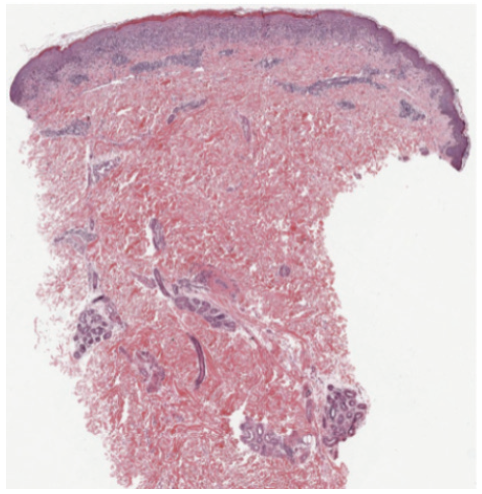

PLC presents as recurrent crops of spontaneously regressing erythematous to purpuric papules. These papules are commonly scaly as compared with the lesions in PLEVA, which are commonly crusted, ulcerated, and occasionally vesicular or pustular. The lesions often regress over weeks to months; however, patients will commonly relapse. It is hypothesized that the distribution of the lesions is more important than the acute or chronic nature. Patients with a diffuse distribution of lesions tend to have a shorter average disease course of approximately 11 months, compared with patients with a peripheral distribution who have a longer average disease course of approximately 33 months.1 Diagnosis requires histopathologic evaluation. PLC exhibits a superficial perivascular interface dermatitis. Lymphocytes predominate in the infiltrate, although neutrophils are sometimes present as well. Within the epidermis, there is focal parakeratosis and evidence of damage that ranges from edema to extensive epidermal necrosis. Frequently, there is extravasation of erythrocytes. All these changes are blunted in more chronic lesions.1

The patient had a punch biopsy from the left thigh that was consistent with PLC (Figures 5–8). She was started on 3 courses of azithromycin over 6 weeks and referred for phototherapy. She received phototherapy 3 times weekly for approximately 1.5 months. After this course of phototherapy, she had developed no new lesions and old lesions were healing, although they did exhibit post inflammatory hyperpigmentation. She was started on doxycycline 100 mg daily.